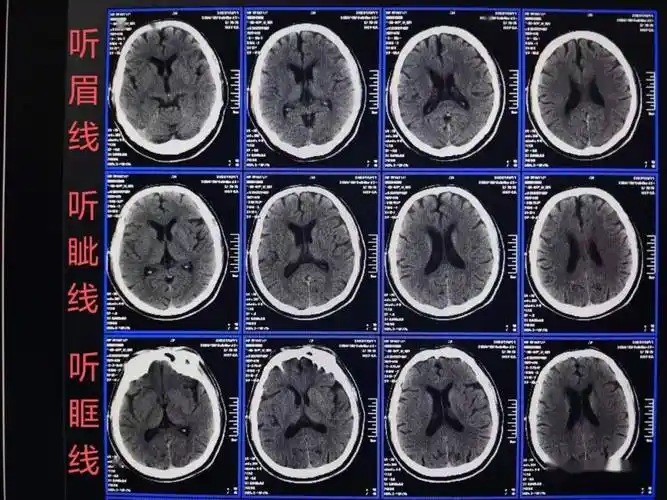

头颅ct扫描时如何打角度才能看得更多更清晰